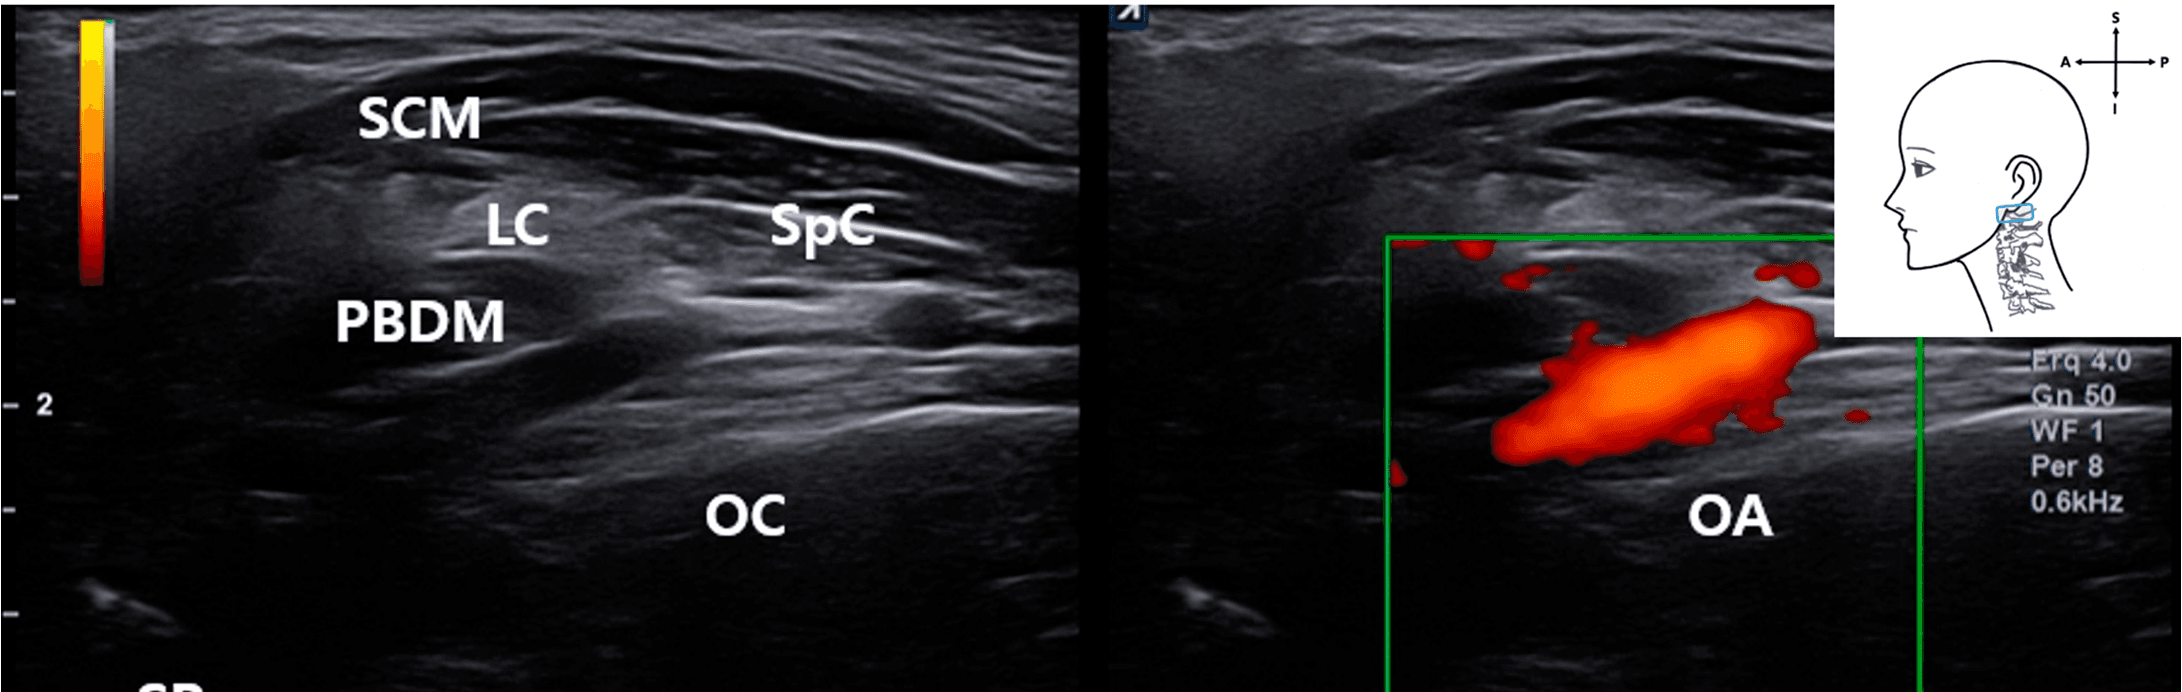

도플러초음파를 활용하여 척추동맥(vertebral artery)과 후두동맥(occipital artery) 등 주요 혈관 구조의 실시간 혈류 확인도 프로토콜에 포함시켰습니다. 이는 시술 중 혈관 손상 위험을 최소화하기 위한 안전장치 역할을 합니다.

안면마비 - Live dual doppler ultrasound in a living patient confirming visualization of the Figure 5. Live dual doppler ultrasound in a living patient confirming visualization of the VA. Real- time vascular flow was detected in the deep cervical plane, suggesting that this structure can be monitored during ultrasound-guided FN interventions. Color flow mapping (green box) confirms arterial characteristics. Blue rectangle, probe position.

특히 고해상도 초음파로 제1경추 횡돌기와 후궁을 안정적으로 시각화할 수 있었고, 프로브를 상방으로 기울이는 heel-toe 기법을 통해 척추동맥을 상부 경추 부위에서 일관되게 확인할 수 있었습니다.

실시간 도플러초음파를 통해 생체에서 척추동맥과 후두동맥의 혈관 흐름을 확인하여 초음파 유도 시술 중 혈관 구조 식별이 가능함을 입증하였습니다. 컬러 플로우 매핑을 통해 동맥의 역동성을 확인하고 인접한 비혈관 구조와 명확히 구별할 수 있었습니다.